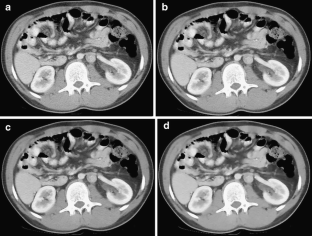

Fig. 1